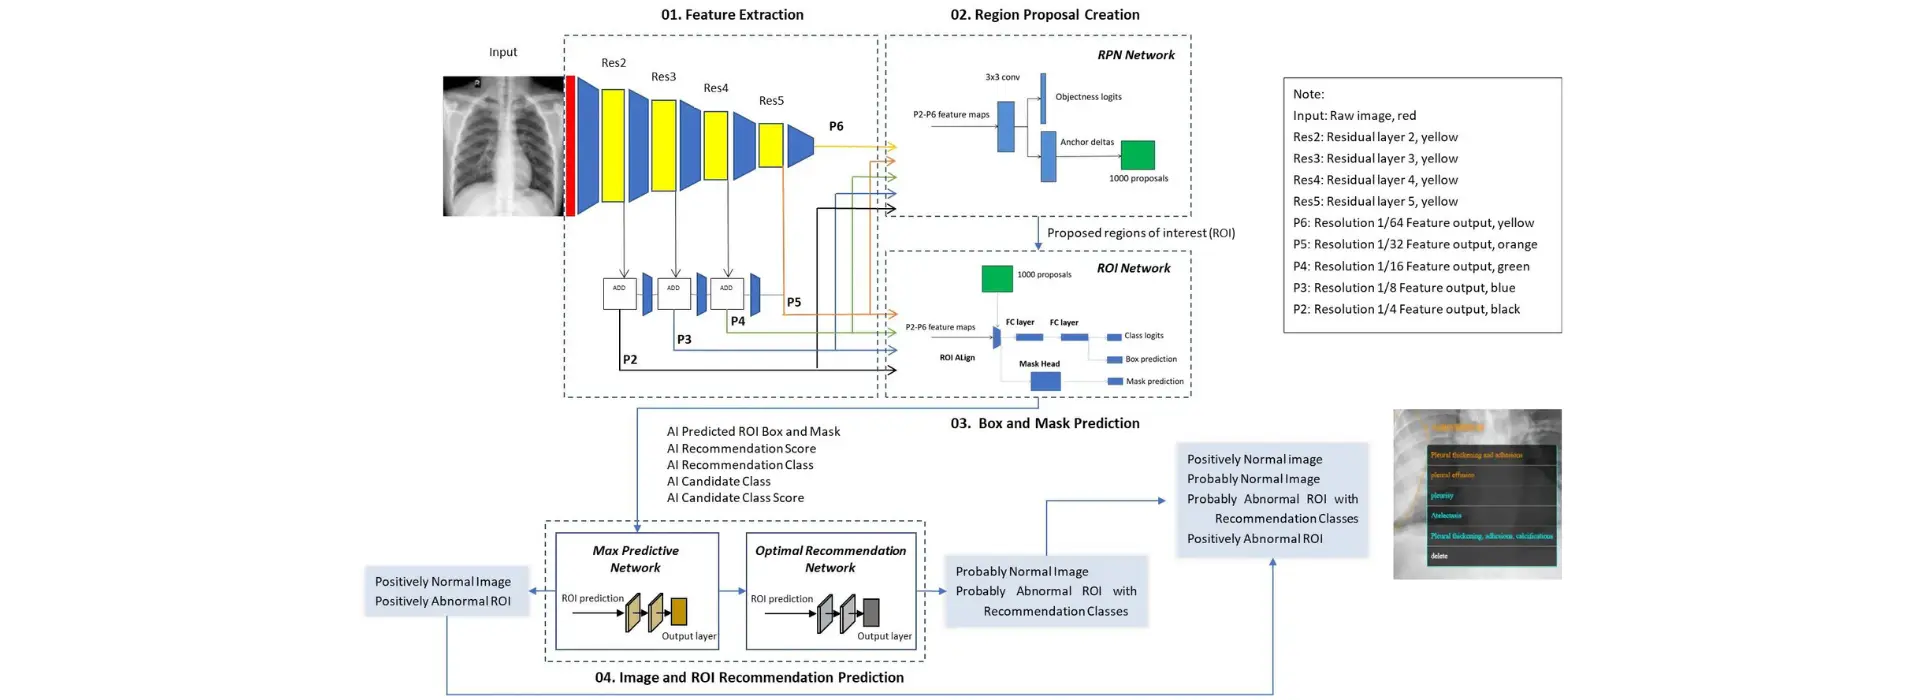

Overview of SIFT™

Caddie’s SIFT™ is the only fully automated annotation tool in the market capable of identifying 66 comorbidities on Chest X-ray and 44 abnormalities on Chest CT simultaneously. Designed specifically for chest X-ray and CT imaging, SIFT™ provides rapid, accurate, fine-grained image labeling and annotation to assist annotators in identifying abnormalities and their corresponding boundaries.

Providing Initial Type of Abnormalities SIFT™ can automatically detect and classify ROIs into specific types of abnormalities (“Predicted Disease”). It can predict 66 different types of abnormalities and recommend several options if the original prediction score is not high enough. Annotators can easily confirm or reject the type using SIFT’s interface.

- Compliance with Standards: SIFT™ complies with medical standards, with 90% of its disease lexicons matching MedDRA UMLS CUI coding and the remaining 10% aligning with Radiopaedia.

- Boundary Coordinates: SIFT™ can automatically draw ROI boundaries and predict location coordinates. Annotators can accept or edit the boundaries using the SIFT™ GUI.

- Storing Annotations: Annotators can store abnormality types, boundary coordinates, confidence scores, and recommended options in editable Excel files. AI developers can use these files along with images to train their models.

- Batch Processing: SIFT™ can process a large number of CXRs to generate initial locations and boundaries without human intervention.

- Identifying Additional Abnormalities: SIFT™ automatically identifies and delineates additional abnormal regions and boundaries on chest X-ray images.

- Confidence Scores: SIFT™ generates confidence scores for each AI-specified ROI and predicted disease.